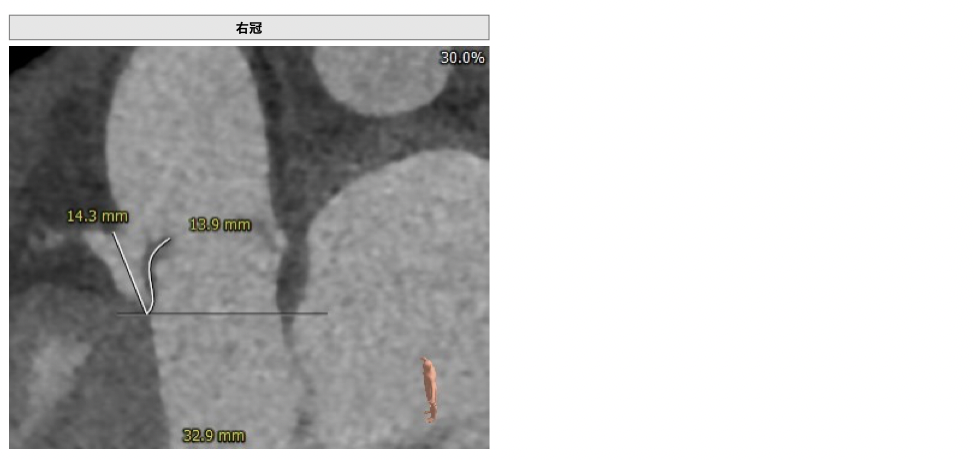

CT检查

③左冠高度不高,且瓣叶冗长,达冠脉开口层面,且冠脉存在狭窄,存在冠脉阻塞的风险;

确保冠脉安全,拟采取PCI+TAVR一站式手术策略,因患者右侧股动脉钙化严重、入路狭窄,拟采取无鞘法从右股动脉穿刺入路,选用20mm球囊预扩、L23号VenusA-Valve瓣膜、采用VenusA-Plus输送系统确保瓣膜的精确释放,瓣膜释放后结合造影和超声情况,决定是否后扩。